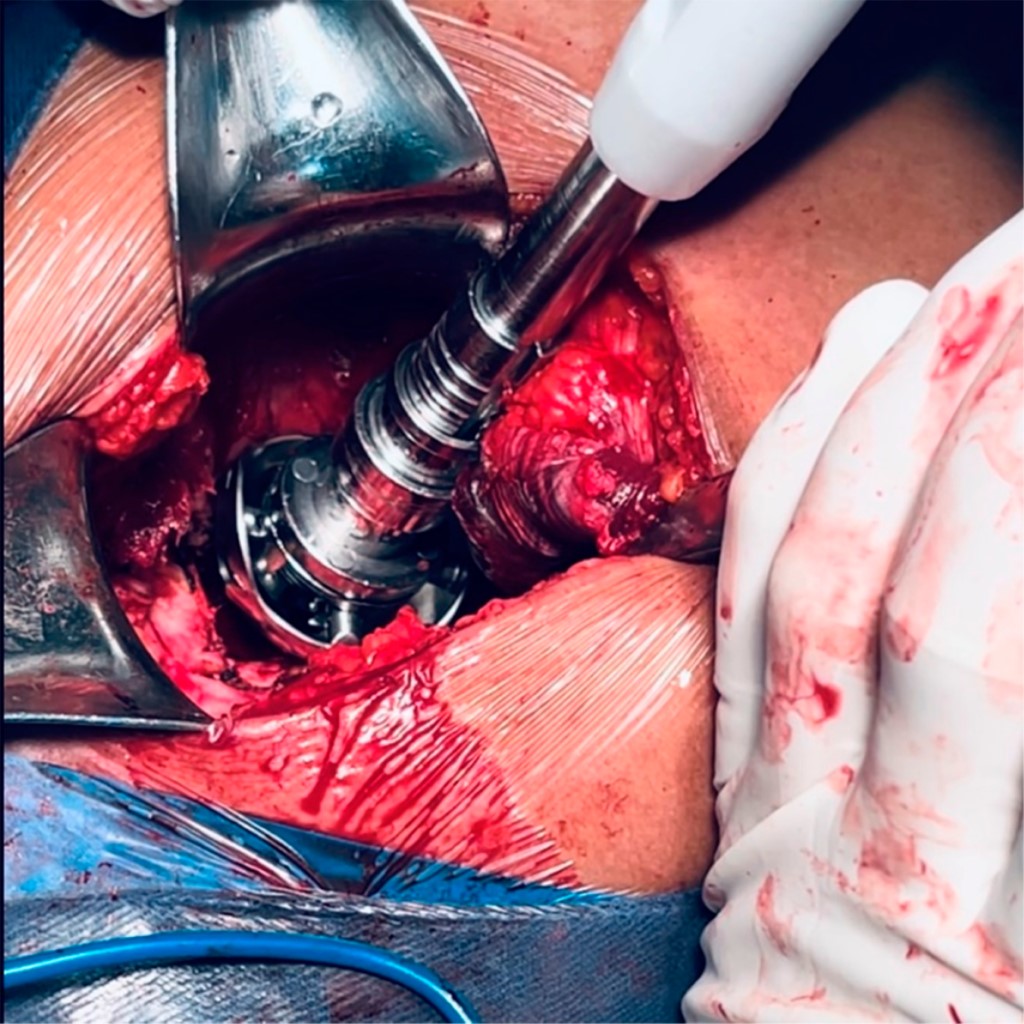

Tiempo femoral: se colocan separadores de Bennet sobre trocánter menor y mayor con la extremidad inferior en flexión de 90°, aducción y rotación externa para exponer el canal femoral, al igual que el acetábulo, el fémur no está exento de presentar características anatómicas distintas, en este caso anteversión pronunciada, canal medular estrecho y cuellos con angulación en valgo (Figura 7). Se realiza resección de hueso esponjoso con osteótomo de canal medular y se procede al rimado femoral con sistema de rimas proximales, se colocan implantes definitivos, vástago #1, copa acetabular 46 mm, inserto 46 mm para cabeza 28 mm y cabeza 28 mm estándar de cerámica (Figura 8). La brecha que existe entre el acetábulo y fémur, aproximadamente de 8 cm, impide la reducción (Figura 9).

Figura 8